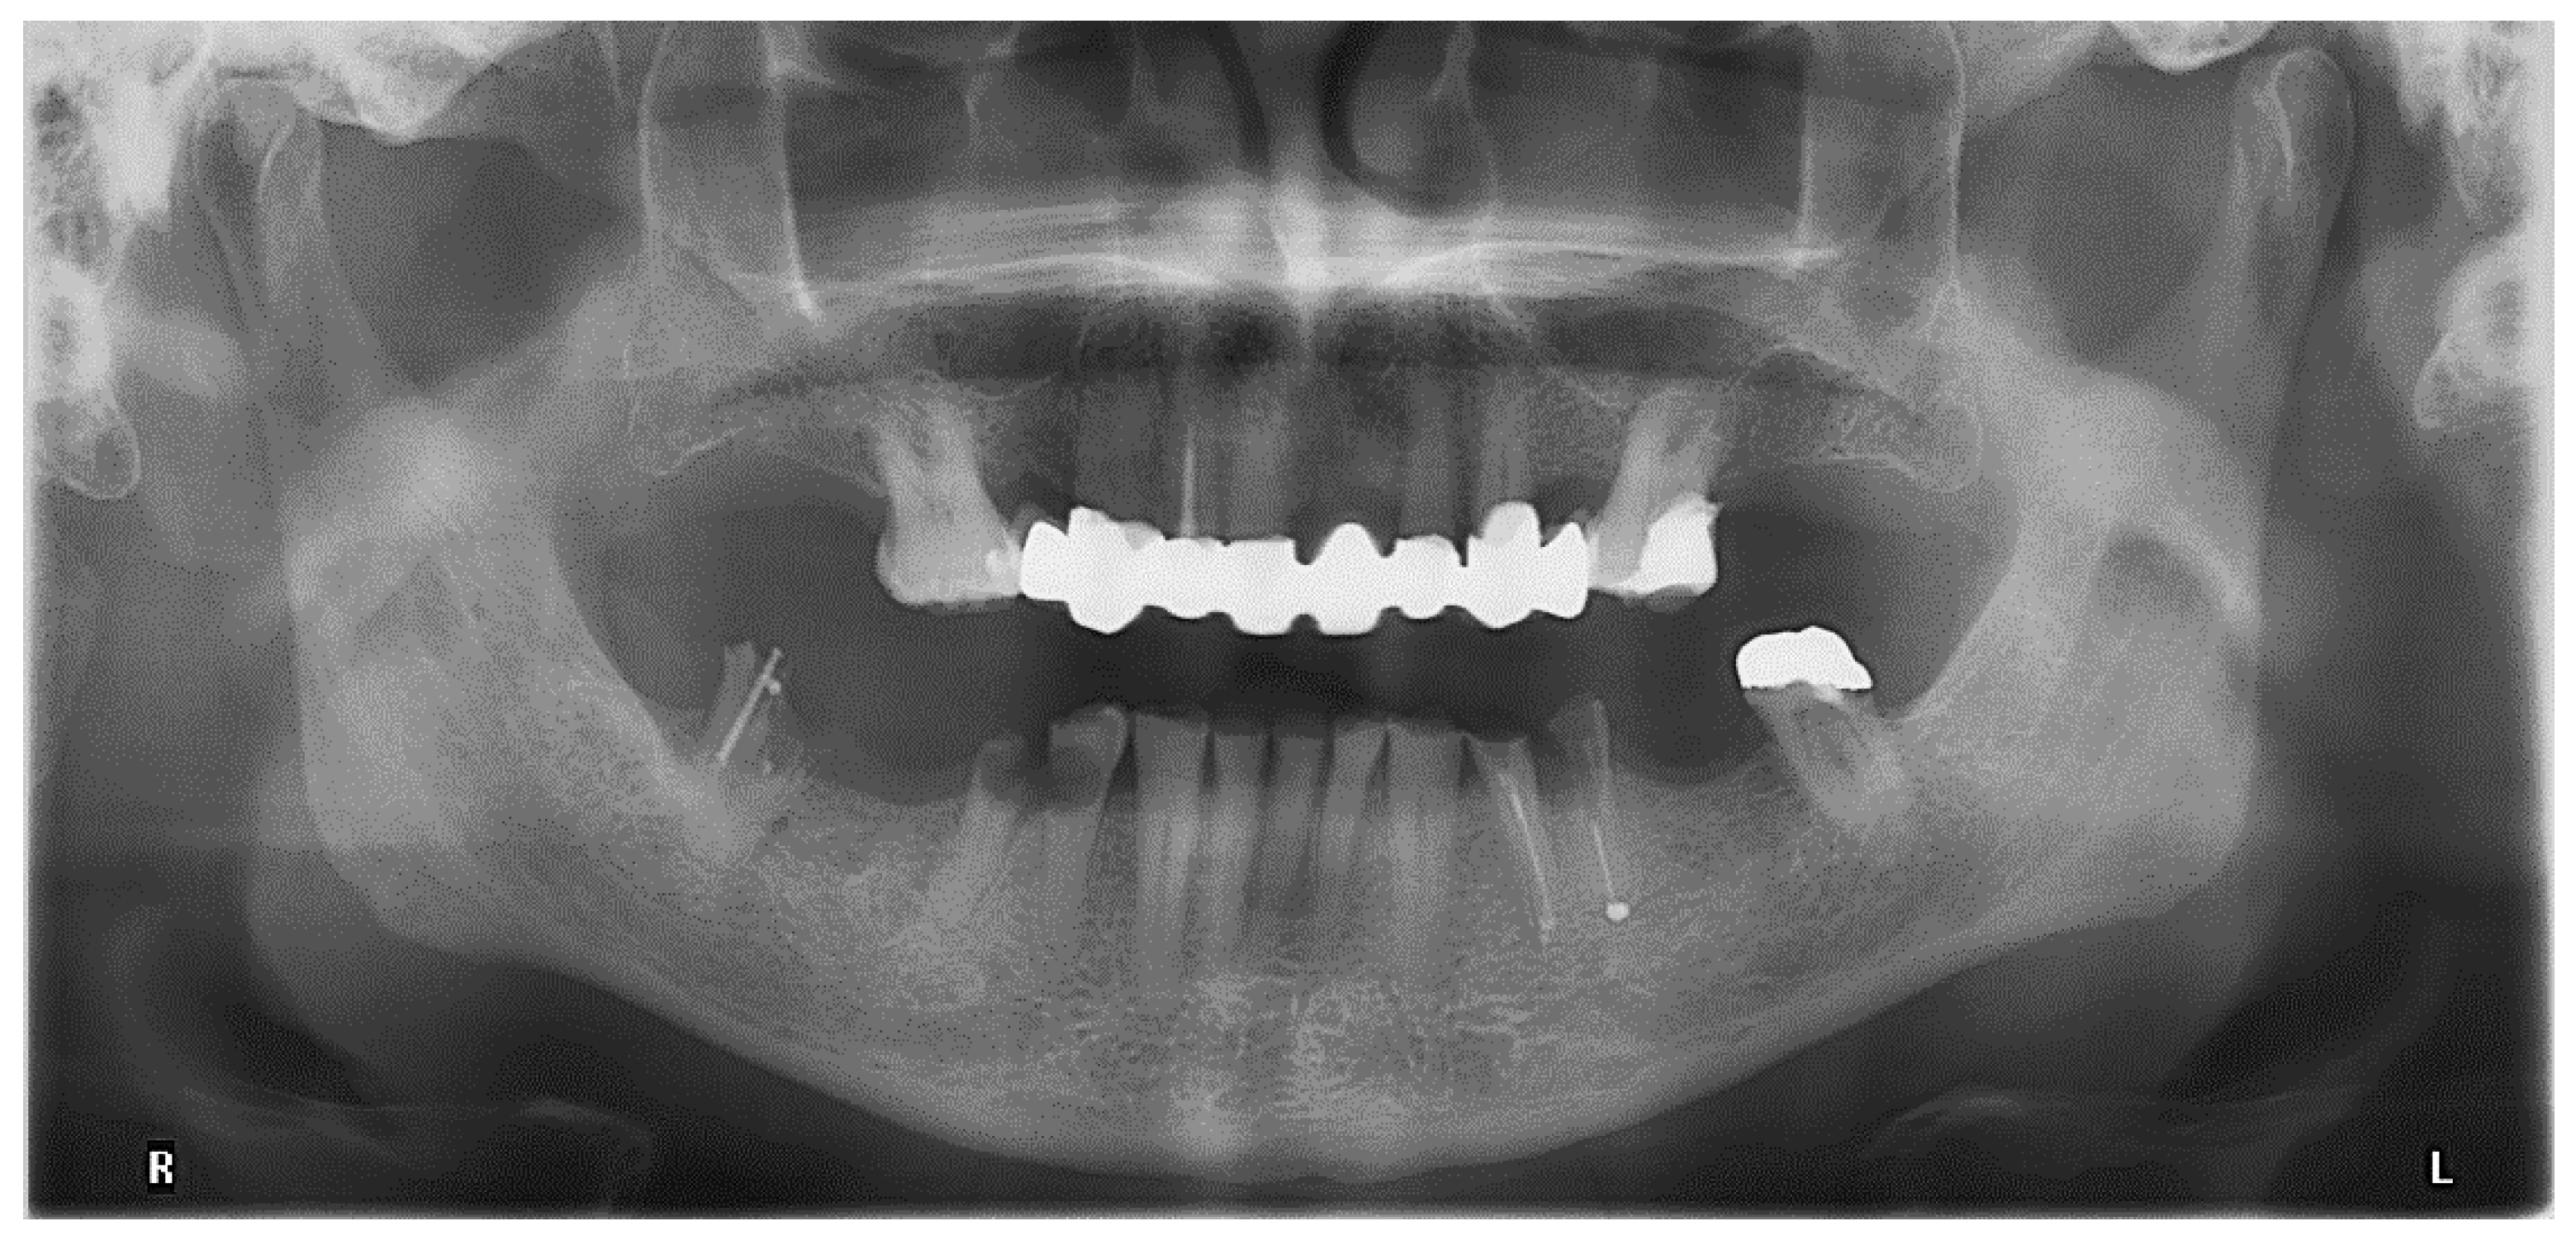

3. Case Report

- Removable multi-unit bridge including all remaining teeth and implants, fabricated from zirconium dioxide telescopic crowns and a veneered polyaryletherketone (PAEK) framework,

- Single-crown fixed dental prostheses for all teeth; Locator abutments on both implants and insertion of a clasp-retained RDP with PAEK framework,

- Locator abutments on both implants, single-crown FDPs on the remaining lower molar teeth, insertion of a tooth-colored and tooth-shaped monolithic RDP fabricated from POM with minimally invasive preparation of the lower anterior teeth (experimental character in long-term endurance).